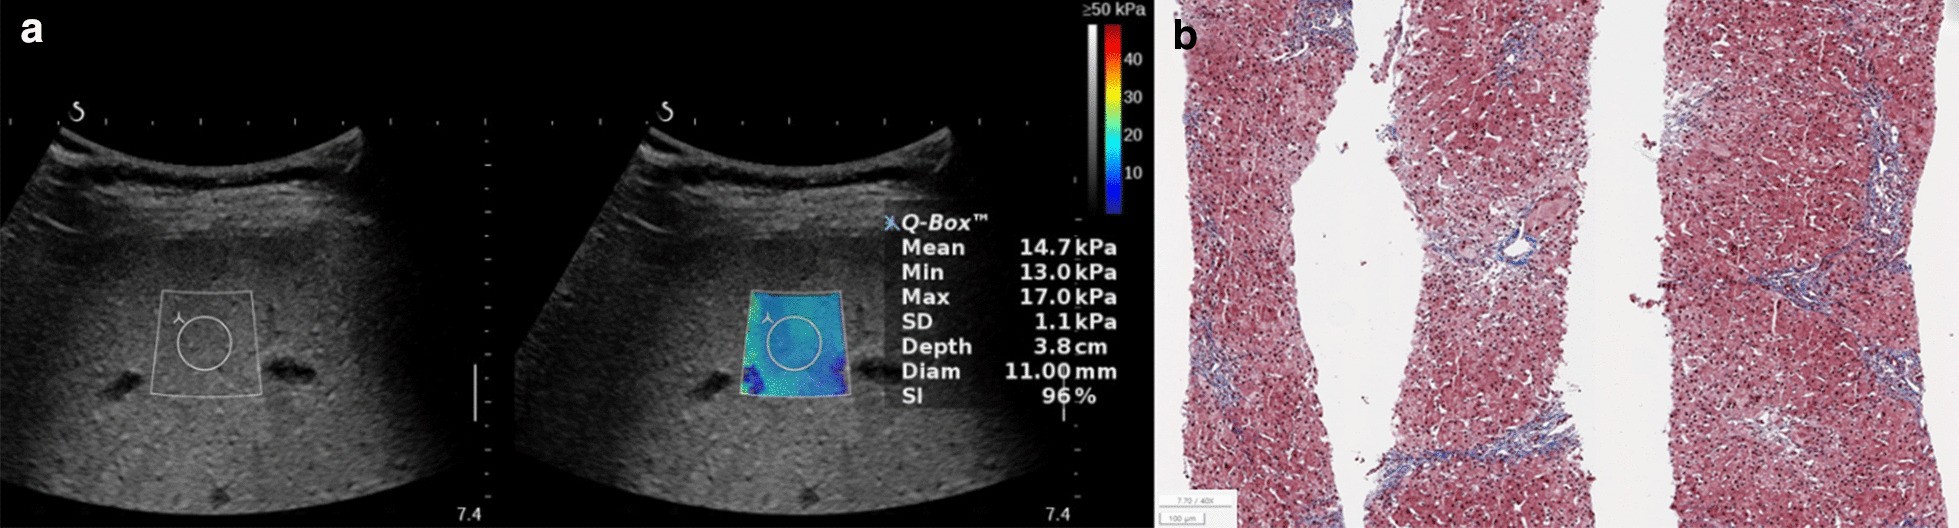

Fig. 3

Hemophagocytic lymphohistiocytosis combined with the hepatitis in a 2.2-year-old boy. The serum biochemical marker levels were as follows: AST to platelet ratio index (APRI), 14.5; AST to alanine aminotransferase ratio (AAR), 0.8; and fibrosis-4 (FIB-4) score, 0.4. a Two-dimensional shear-wave elastography (2D-SWE) showing diffuse hyperechoic parenchyma with 14.7 kPa liver stiffness value. b Histopathologic specimen showing moderate lobular necroinflammatory activity and few portal fibrosis with METAVIR score, F2